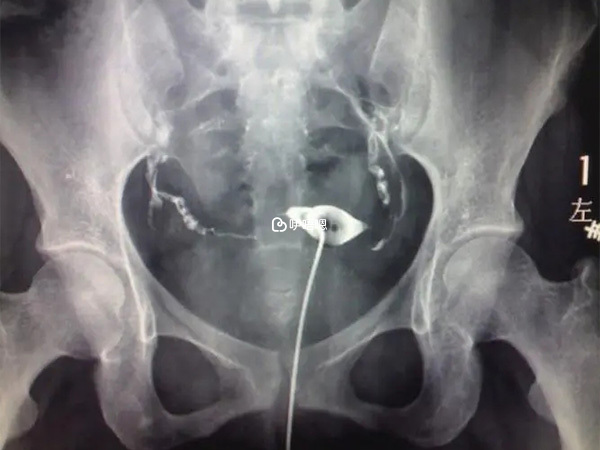

也不知道是不是排卵期B超無法清晰看出子宮情況,反正每次B超都沒看出來子宮裡面有肌瘤或積液,子宮是前位的。10年4月份,做了輸卵管碘油造影。因為之前兩次藥流都是自己買藥吃的,吃完後也沒有去醫院複查,一年沒受孕,怕是管子有問題。我以為造影很簡單,就跟從口腔喝水那麼簡單,那天早飯都沒吃就一個人跑去了,結果通液的時候一直不舒服,不痛,但是很難受,小肚子漲漲的。做完的時候我臉色刷白,一下床腿就軟了,把醫生給嚇了一跳,說你這個人體質這麼虛的啊。檢查結果仍然是好的,沒看出來任何問題。